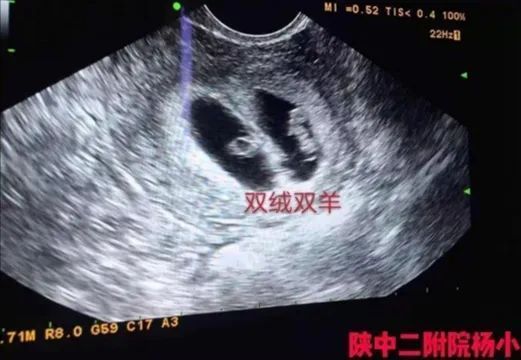

看着患者恳求的目光,杨小颀一边鼓励安慰,一边邀请到超声科主任杨兵社进行会诊,确定患者分裂的胚胎为双绒双羊。双绒双羊就是双绒毛膜双羊膜囊,不是两个宝宝共用一个胎盘,就是双卵双胎,两个宝宝分别在自己的羊膜腔内。这种情况,一般多数是两个卵,两个胚胎,也有一个卵两个胚胎的情况,但是是少数。